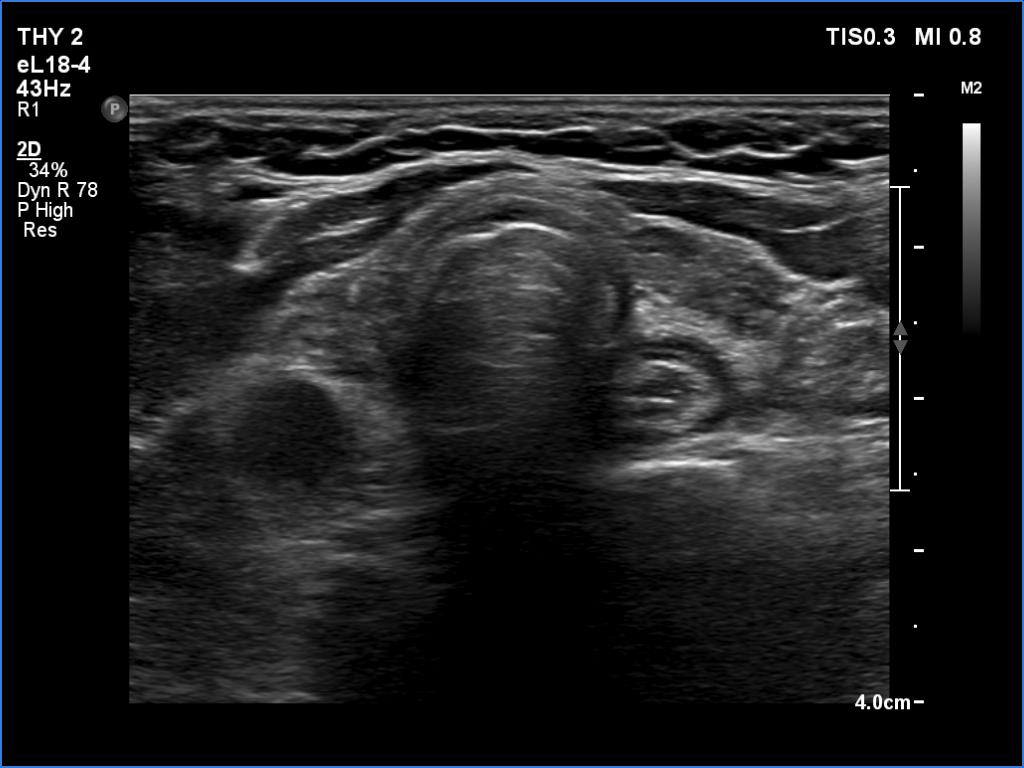

Ultrasonography. The thyroid was atrophic and hypoechoic. There was a hypoechoic mass under the lower pole of the left lobe.

Histopathology disclosed parathyroid adenoma.